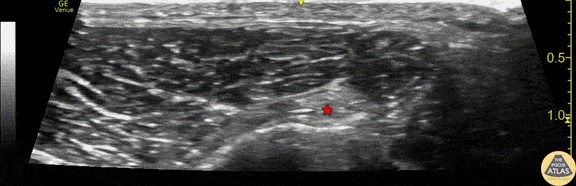

Demonstration of the anatomy of the common peroneal nerve at the level of the proximal fibula. This image was obtained with the linear transducer placed in a transverse orientation on the lateral aspect of the fibular head. The nerve (*) is seen just superficial to the hyperechoic fibular cortex. Drs. Sam Paskin-Flerlage, PGY4 and Michael Heffler, PGY3 Denver Health Residency in Emergency Medicine